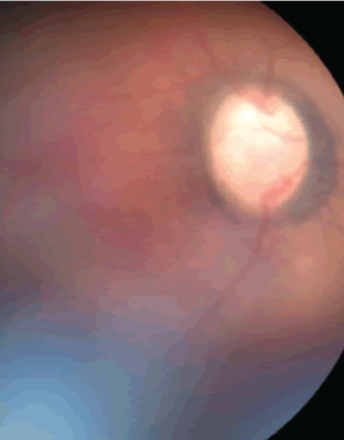

Ocular surface squamous neoplasia treated with topical chemotherapy

A man in his 90s presented to clinic with a conjunctival lesion on the right eye noticed two months prior. The patient denied pain but endorsed worsening blurry vision. The patient’s past medical history was significant for skin cancer on the right ear removed 3 years ago, and a history of ocular surface lesion removal on one eye approximately 20 years ago that was negative for any neoplasia. Slit lamp photograph revealed a gelatinous and opalescent lesion suspicious for ocular surface squamous neoplasia (OSSN) and the high-resolution optical coherence tomography (HROCT) cut (arrow)